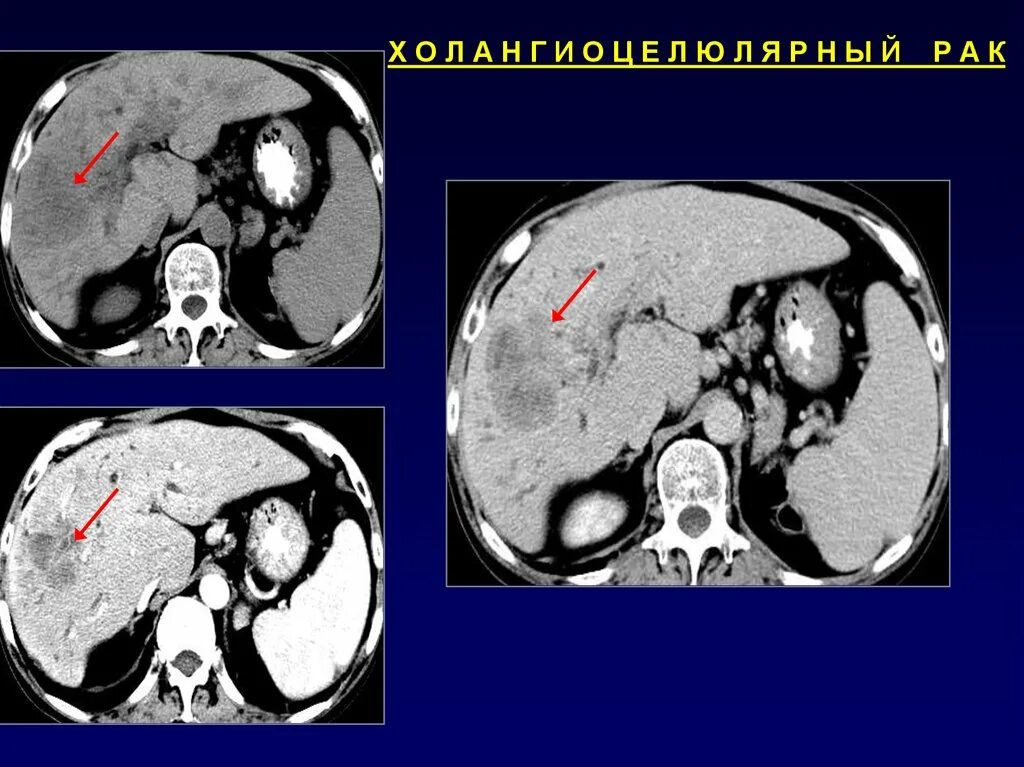

Кт х